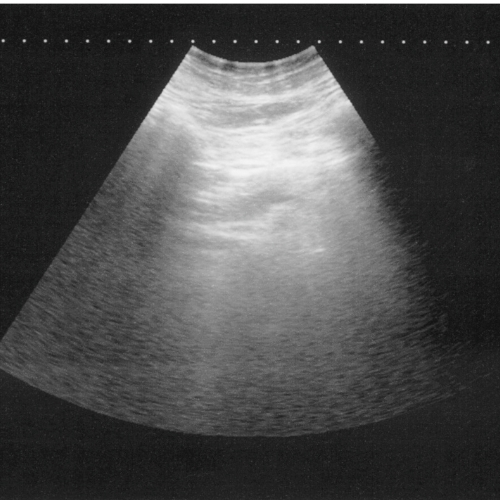

Ultrasonography is used primarily for diagnosing soft tissue injuries. It can visualize damage to tendons, ligaments, and bony surfaces in areas that are difficult to radiograph. Ultrasound can identify lesions within tendon structures (see image at right), helping to give a prognosis for the required lay-up and healing time. It can be used for guided needle placement in treating sensitive areas such as lesions in the neck, spine, and pelvis. Abdominal abnormalities can often be viewed and identified. Ultrasound is also commonly used for reproductive work, making it possible to identify a pregnancy as early as 13 days.